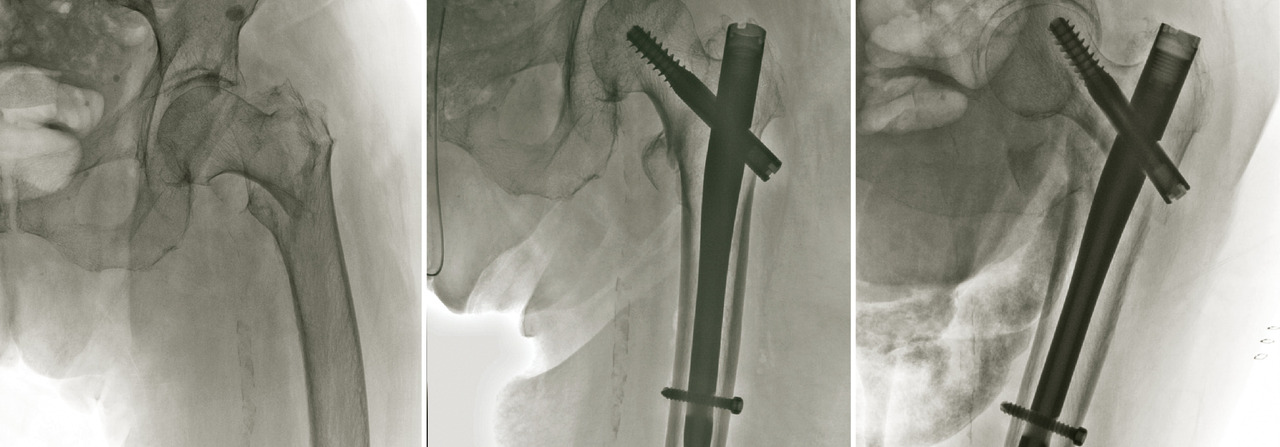

En cas de fracture du massif trochantérien, compte tenu du faible risque de nécrose, la solution chirurgicale est presque toujours l’ostéosynthèse. Cette dernière a pour but de fixer la fracture une fois la réduction de celle-ci obtenue. Il peut s’agir d’une vis-plaque ou d’un clou fémoral proximal verrouillé type clou gamma (fig. 15). Dans les cas de fracture particulièrement instable ou lorsque la fracture s’étend vers la diaphyse, l’ostéosynthèse par clou est recommandée.